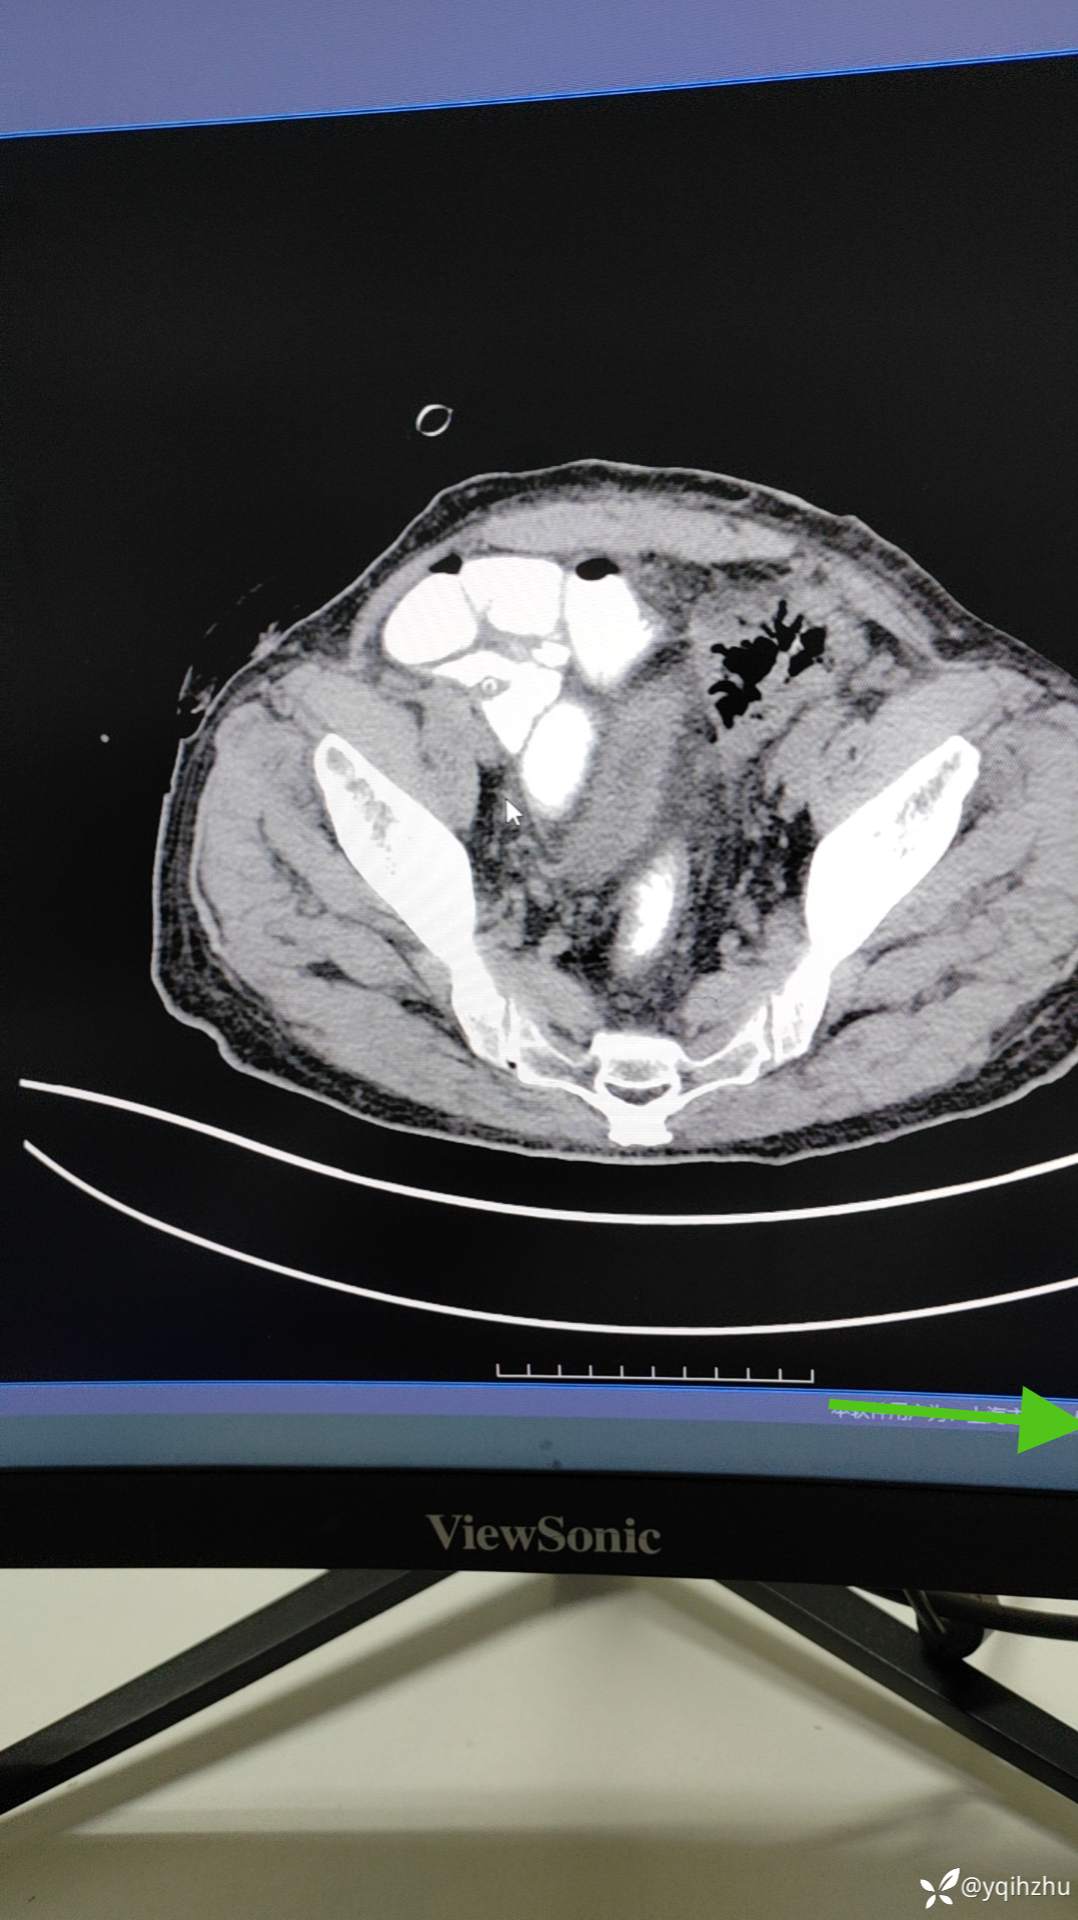

患者老年男性,82岁,急性肠梗阻入院,当时急诊行肠镜下支架植入术,术后3周在全麻下行腔镜下乙状结肠癌根治术,手术顺利,术中见乙状结肠和直肠肠管无明显水肿,给于一期切除,吻合口吻合器切除+浆肌层保埋,骶前部置双套管引流。术后第3天解便和排气,给于饮水,但2小时后出现腹胀不适,给于禁食,胃肠减压,等营养保守治疗,目前术后第15天,给于碘海醇口服后6小时造影。图片如下